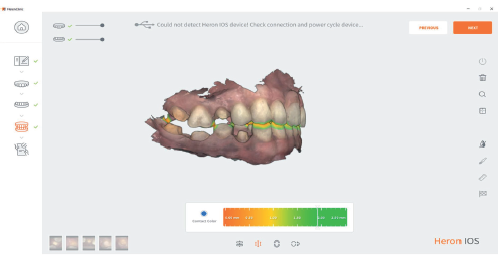

Occlusal Clearance

This tool helps you check the clearance before exporting the case in order to help you treat your crown and bridge patients in an effective and predictable manner.